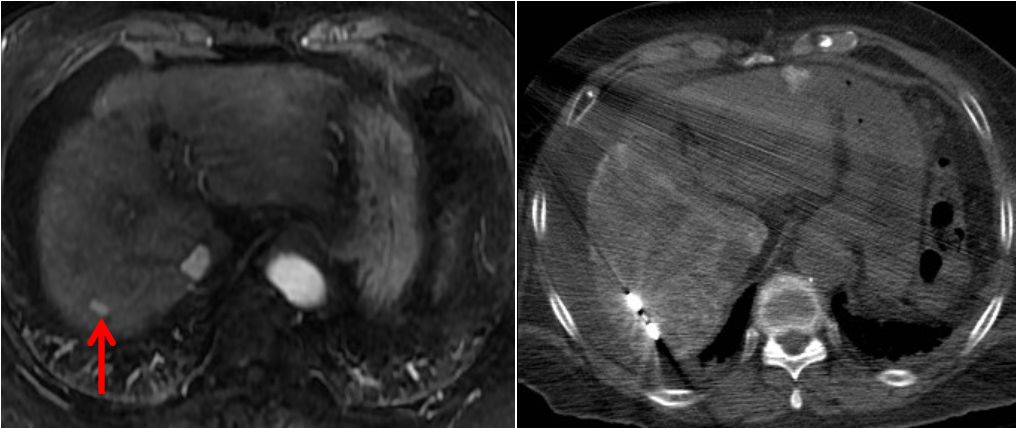

由于肝脏特殊的生理解剖,临近危险器官的特殊部位以及影像显示不清的肝肿瘤,一直是影像引导下经皮消融治疗的难点或“禁区”。 近日,我院放射科介入病房邵海波教授、田玉龙主治医等在麻醉科的大力配合下,为一名复杂的肝癌患者进行了影像引导下的经皮微波消融治疗。手术仅历时1.5小时,术后3天患者即顺利出院。 患者为62岁女性,半年前诊断为原发性肝癌,为肝左叶单发病灶,曾行经导管肝动脉化疗栓塞和微波消融治疗,术后病灶完全灭活。本次入院MRI检查发现新发肿瘤,肝内共有4个活性病灶,分别位于心缘旁、膈顶、胆囊旁等“危险部位”,血供较差,TACE治疗控制不佳,经详细讨论,决定采用经皮微波消融治疗。由于病变位置特殊,加之平扫CT或超声均不能清晰的显示全部病灶,大大增加了消融治疗的难度和风险。术中,治疗团队采用腹水隔离、CT/超声双引导进针监测、解剖标记定位、低功率间断消融等多种辅助手段相结合,对全部4处病灶进行了安全、精准的微波消融治疗,手术历时1.5小时,术后3天患者顺利出院。 图1. 临近心脏的膈顶部病灶,水隔离保护下消融 图2. 临近包膜的膈顶部病灶,水隔离保护消融 图3. 紧邻胆囊病灶,超声引导和监测下低功率间断消融 图4. CT和超声均显示不清的病灶,采用CT引导解剖标记定位消融 图5.肿瘤消融治疗是指利用消融治疗针穿刺肝肿瘤,针尖能够产生电磁波而使周围组织升温至80度以上的高温,从而杀灭肿瘤。 图6.危险部位肿瘤是指当肿瘤靠近膈顶、心脏、胃、肠管、胆囊、以及肝门部等部位时,对肿瘤进行消融就容易损伤相应的器官,引起并发症。因此这些部位的肿瘤称为危险部位肿瘤。 此病例癌症病灶位于膈顶部、心脏旁、胆囊旁、肝门部、大血管附近,肝边缘近胃肠道、外凸近腹壁,治疗难度大,技术复杂、成功率低、风险高。介入病房开展水隔离技术、胆管冷却技术、术中引流技术、造影增强定位技术、解剖标记定位技术、复合影像导航穿刺和监视技术等新技术对危险部位和复杂病灶进行成功的经皮消融治疗,几乎做到肝脏肿瘤消融无禁区、无死角。 近年来,影像引导下经皮微波消融治疗已成为肝癌/肝转移癌、肺癌、肾癌等实体肿瘤最为有效的微创治疗手段之一,具有创伤小、恢复快、疗效确切、可重复治疗等优点。据统计,2018年,放射科介入病房利用各种辅助技术处理复杂或高危部位肿瘤41例,疗效显著且无并发症发生,与前期未应用辅助技术的病例相比,完全消融的比率显著提高(93.5% vs.78.5%),不良反应发生率显著降低。 我院放射科介入病房自2004年开始开展影像引导下肝癌的射频/微波消融治疗,在放射科副主任苏洪英教授的领导下,不断突破技术难点,治疗水平逐年提高。科室选派技术骨干到国外学习先进技术,其中本例手术的术者邵海波教授就是在我院中青年骨干培训计划的支持下,在哈佛医学院/麻省总医院进行了为期近2年的消融治疗培训和研究后,回国将所学更好地应用于临床。目前,科室在影像引导下经皮肝肿瘤微波消融领域处于国内领先水平。